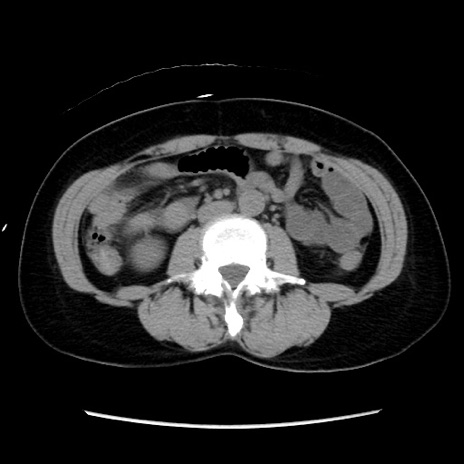

症例10(横断像)

【症例】 50歳代女性

【主訴】 腹痛

【現病歴】前日生レバーを食べた。今朝に排便あり。 昼前に突然発症の腹痛を生じ、当院救急外来を受診した。

【既往歴】 子宮筋腫にてで子宮全摘後

【身体所見】 意識清明、腹部:平坦、軟、下腹部やや左を中心に圧痛・反跳痛あり、筋性防御あり

【データ】WBC 7800、CRP 0.07